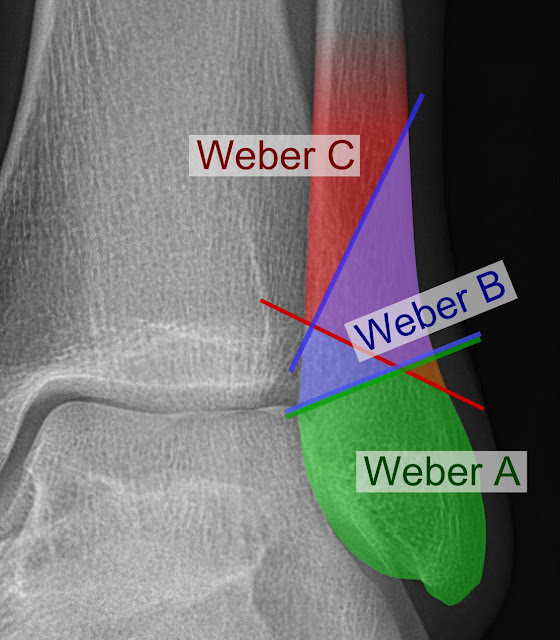

Ankle Fractures Danis er Classification Everything You Need To